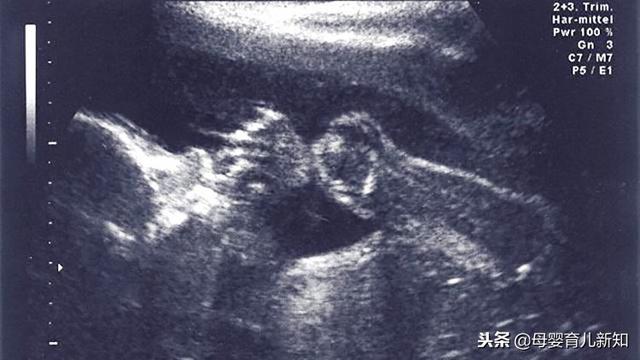

一、3个月就能辨性别

3个月的胎儿就像一个小精灵 , 此时已经可以初步分辨出五官、眼皮 。 因为皮肤是透明的 , 所以可以从外部看到皮下血管和内脏等 。

此时的宝宝已有了输尿管 , 胎儿可进行微量排泄了 。 同时指甲、眉毛和头发也长出来了 。

不过 , 要想观察得更加清楚 , 可以5个月的时候再进行辨别 。